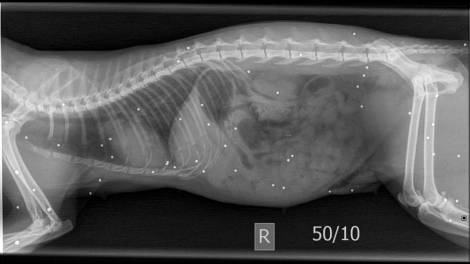

Att ieħor xokkanti ta’ moħqrija fuq l-annimali f’Malta. Kienet l-Organizzazzjoni Happy Paws Malta, li fost oħrajn toffri servizzi ta’...